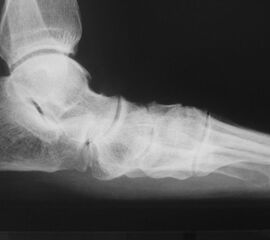

Talonavikular-, navikulocuneiforme- und calcaneocuboidale Arthrosen, also Arthrosen in der Chopart- und Bona-Jäger-Gelenklinie, zeigen sich wesentlich seltener und können in Kombination von Arthrosen aller Gelenke des Mittelfußes auftreten. Die Diagnostik beinhaltet grundsätzlich die ausführliche Untersuchung des gesamten Fußes im Stehen, im Liegen und beim Gehen. Ein Röntgenbild des Fußes im Stehen in zwei Ebenen, ergänzend eine schräge Aufnahme, sowie Saltzman und OSG-Bildgebung sind für die Diagnose und Therapieplanung essentiell. Bei Planung eines operativen Eingriffes sollte eine Computertomographie des gesamten Fußes durchgeführt werden. Zunächst sollte die konservative Therapie mittels Schmerzmedikation, Infiltration, Manueller Therapie, Einlagen, Schuh-Modifikation, Orthesen, orthopädischem Schuhwerk und ggf. eine Strahlentherapie voll ausgeschöpft werden. In zweiter Linie steht die operative Therapie. Chirurgische Eingriffe beinhalten typischer Weise die selektiven Arthrodesen der betroffenen Mittelfußgelenke. Hier wird meist die mediale Säule behandelt, die Arthrodesen der mobileren lateralen Säule sind ein Thema in der Diskussion 2.

Die Diagnostik beinhaltet die komplette klinische Untersuchung des Patienten bei entkleidetem Unterkörper mit Funktionstests, Abtasten der entsprechenden Gelenkreihen (Chopart, Bona Jäger und Lisfranc) und Überprüfung der Beweglichkeit der Tarsometatarsalgelenke mit dem Klaviertasten-Test 11. Beurteilt werden Fußformveränderungen, osteophytäre Anbauten, sowie eine mögliche Verkürzung des M. gastrocnemius-soleus-Komplexes mit Hilfe des Silfverskjöld-Tests 12. Es werdemRöntgenaufnahmen des Fußes im Stehen in 2 Ebenen und ergänzend eine Schrägaufnahme des Fußes durchgeführt. Bei Fußfehlstellungen erfolgt zusätzlich das Röntgen des oberen Sprunggelenks im Stehen und eine Saltzman-Aufnahme 13.

Bei Nachweis von degenerativen Veränderungen ist für eine Therapie- und ggf. Operationsplanung eine Dünnschicht-Computertomografie des Bereiches notwendig. Darüber hinaus sind unter einer Röntgendurchleuchtung durchgeführte, diagnostische Infiltrationen mit einem lokalen Anästhetikum möglich, um den Ort der Beschwerden genauer differenzieren zu können.